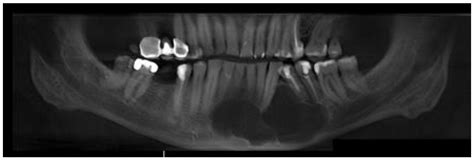

Diagnosis of a traumatic bone cyst typically involves a combination of clinical examination and radiographic imaging. Dental X-rays, such as periapical radiographs or panoramic radiographs, are commonly used to visualize the cyst. In some cases, a computed tomography (CT) scan or magnetic resonance imaging (MRI) may be recommended for a more detailed evaluation.

The radiographic appearance of a traumatic bone cyst can vary, but some common features include:

• Well-defined Radiolucent Lesion: The cyst appears as a well-defined, radiolucent area on dental radiographs.

• Scalloped Margins: The margins of the cyst may be scalloped, giving it a characteristic appearance.

• Cortical Bone Expansion: In some cases, the cyst may cause expansion of the cortical bone.

• No Internal Structures: Unlike other cysts, a traumatic bone cyst typically does not contain internal structures such as septa or calcifications.